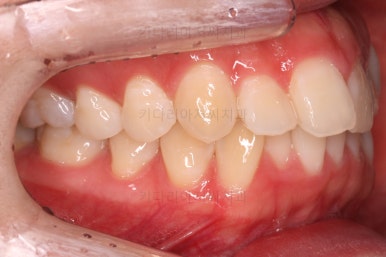

치열만 보면 매우 가지런해진 것 같죠?

이때가 대략 8개월 정도 지났을 때의 모습인데요.

어차피 비대칭은 수용해야 되고, 중앙서노 100% 안맞으니 이정도만 해도 매우 양호한 것 같죠?

하지만 해볼만한 치료는 상당히 많습니다.